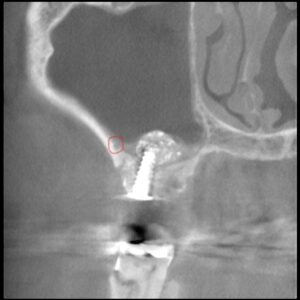

後上歯槽動脈を避けたラテラルスリット法50代男性サ…

後上歯槽動脈の存在がサイナスリフトオペ を不可能にする場合もあります。 抜歯した穴からラテラルスリット法によるサイナスリフトを行いました。 侵襲も少なく、後上歯槽動脈も傷つけることなくオペを完了しました。 …